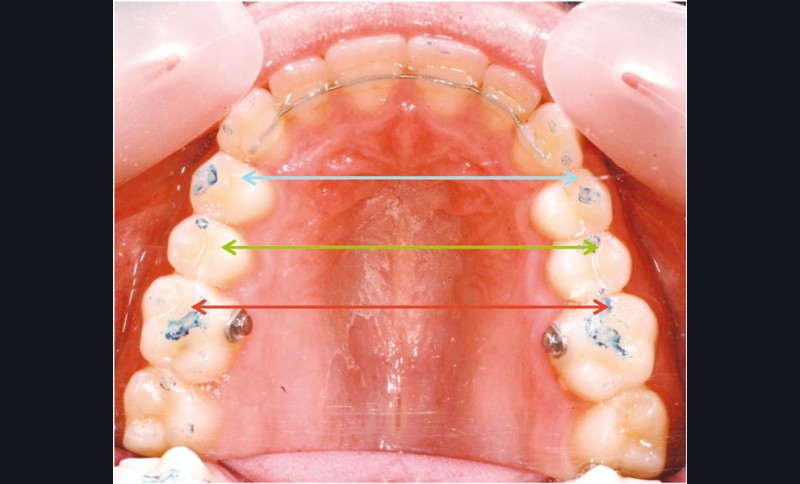

Le cas d’Anthony âgé de 11 ans et 7 mois qui présente une endomaxillie bilatérale associée à un léger encombrement mandibulaire dans un contexte de classe I squelettique hyperdivergente (fig. 1 à 10) est très représentatif de ce que peuvent apporter les forces légères appliquées aux alvéoles dentaires tout en intégrant des torques spécifiques qui permettent de contrôler parfaitement l’orientation radiculaire (fig. 11 à 29).

Le système laisse beaucoup de liberté dans l’interface entre bracket et arc : la vascularisation, et donc le recrutement cellulaire et la reconstruction osseuse s’en trouvent améliorés, la mise en place de l’occlusion se fait sous le contrôle de la matrice fonctionnelle, car les forces engagées restent en dessous de la puissance des forces masticatrices notamment.

Sans aucun appareillage d’expansion, le maxillaire a été transformé et semble avoir été soumis à une disjonction (fig. 30).